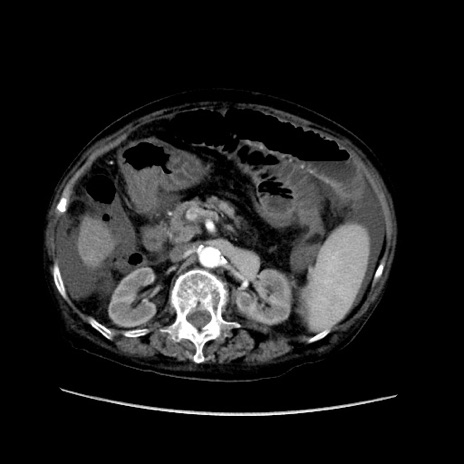

症例31(横断像)

【症例】80歳代 女性

【主訴】腹部膨満感

【現病歴】他院にて肝硬変にてフォロー中。1週間前から便秘、腹部膨満感、臍部腫瘤あり受診となる。

【既往歴】肝硬変

【身体所見】腹部膨隆あり、皮膚変化なし、疼痛なし。

【データ】WBC 4600、CRP 0.25